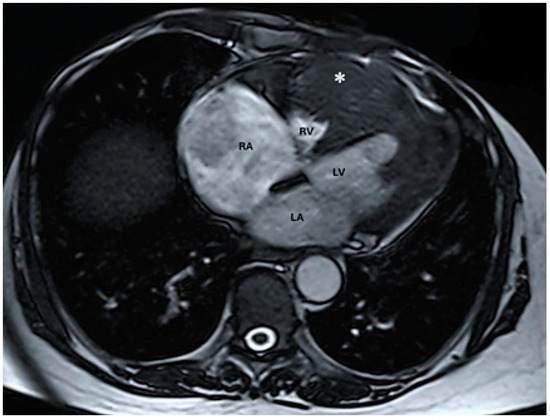

The troponin I level was found to be slightly elevated (90 ng/mL). Coronarography was used to rule out any luminal or anatomical abnormalities. A tumour filling the right ventricle and involving the apex of the left ventricle was identified at transthoracic echocardiography (Figure 3 and Figure 4).

Figure 3. Transthoracic echocardiographic apical four-chamber view: a larger mass (∗) in the right ventricle which also involves the apex of the left ventricle. (Abbreviations: RA = right atrium, LA = left atrium, RV = right ventricle, LV = left ventricle, (∗) cardiac mass.)